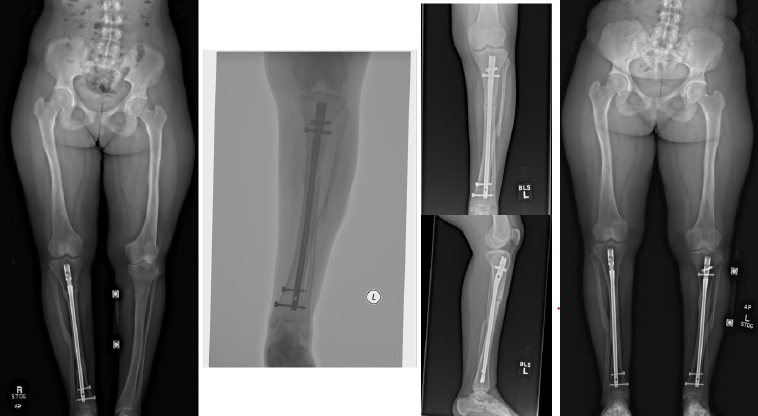

Complications occurred in 5 patients with tibial DC, including 3 cases of hardware removal due to symptomatic prominent interlocking screws and 1 case of delayed union. Complications arose in 4 patients with femoral DC, including 3 cases of nonunion, 1 case of hardware removal due to prominent screws, and 1 case of nonunion and infection (Table 1). There were no cases of peroneal nerve palsy or compartment syndrome. All patients achieved eventual clinical and radiographic union. Pre- and postoperative radiographs of 4 cases are included to highlight the variation in presentation and operative site (Figs. 4-7).

From left to right: Preoperatively, immediately postoperatively, 3 months postoperatively, 9 months postoperatively, and 3 years postoperatively (patient #8).